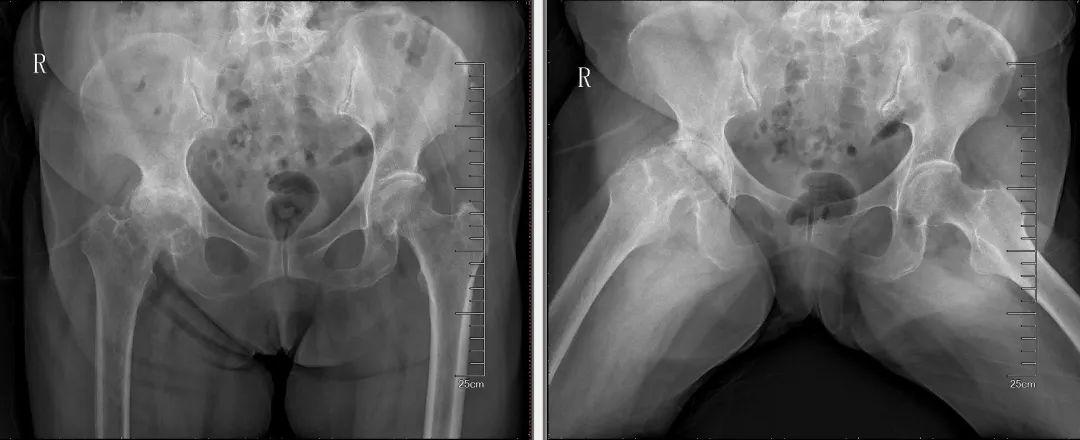

82岁的朱奶奶,今年3月份来到何伟教授门诊。一年前,朱奶奶在其他医院诊断为右侧股骨头坏死,手术前夕,主管医生告知家属,朱奶奶年纪大同时还有心肌缺血,风险太大,希望家属慎重考虑,基于此,家属放弃了手术。在这之后,朱奶奶的病情每况愈下,晚上连翻身都疼痛难忍、举步维艰,只能每天坐着轮椅。一个偶然的机会,朱奶奶了解到何伟教授是治疗此病的专家,便想请何教授开些中药,缓解髋关节炎的疼痛。

于是80多岁高龄的夫妻俩便来到了何伟教授门诊。何伟教授耐心听了朱奶奶的顾虑后,告知朱奶奶:“您的情况不是股骨头坏死,是晚期髋关节炎,非手术治疗很难有理想的效果。尤其是老人家,靠吃药不能解决问题,对于您的情况,最合适的治疗方法是人工髋关节置换手术。没有必要这样忍下去、拖下去,而且髋关节置换手术我们几乎天天做,技术非常成熟,手术时间不到一小时,经过完善的术前检查、评估,有麻醉医生的配合,手术的安全性也很可靠。”